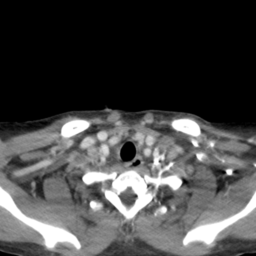

![]() |

| (a) | (b) | (c) | (d) |

Unsupervised Categorization: Our category discovery clusters are generally visually coherent within the cluster and size-balanced across clusters. However, image clusters formed only based on text information (of radiology reports) are highly unbalanced [49], with three clusters inhabiting the majority of images. Note that our method imposes no explicit constraint on the number of instances per cluster. Fig. 6 shows sample images and their top-10 associated key words from two randomly selected clusters (more results are provided in the supplementary material). The LDPO clusters are found to be clinically or semantically related to the corresponding key words, which describe presented anatomies, pathologies (e.g., adenopathy, mass), their associated attributes (e.g., bulky, frontal) and imaging protocols or properties.

The category discovery clusters employing our LDPO method are found to be more visually coherent and cluster-wise balanced in comparison to the results in [49] where clusters are formed only from text information ( radiology reports). Fig. 7 Left shows the image numbers for each cluster from the AlexNet-FC7-Topic setting. The numbers are uniformly distributed with a mean of 778 and standard deviation of 52. Fig. 7 Right illustrates the relation of clustering results derived from image cues or text reports [49]. Note that there is no instance-balance-per-cluster constraints in the LDPO clustering. The clusters in [49] are highly uneven: 3 clusters inhabit the majority of images. Fig. 6 shows sample images and top-10 associated key words from 5 randomly selected clusters (more results in the supplementary material). The LDPO clusters are found to be semantically or clinically related to the corresponding key words, containing the information of (likely appeared) anatomies, pathologies (e.g., adenopathy, mass), their attributes (e.g., bulky, frontal) and imaging protocols or properties.